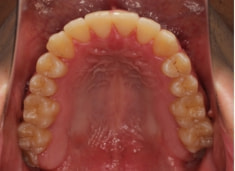

治療前

治療後(2年1ヶ月後)

やはり統計通り、左上3番の埋伏です。

左上2番の歯根吸収が認められますが、保存不可能なレベルではありません。